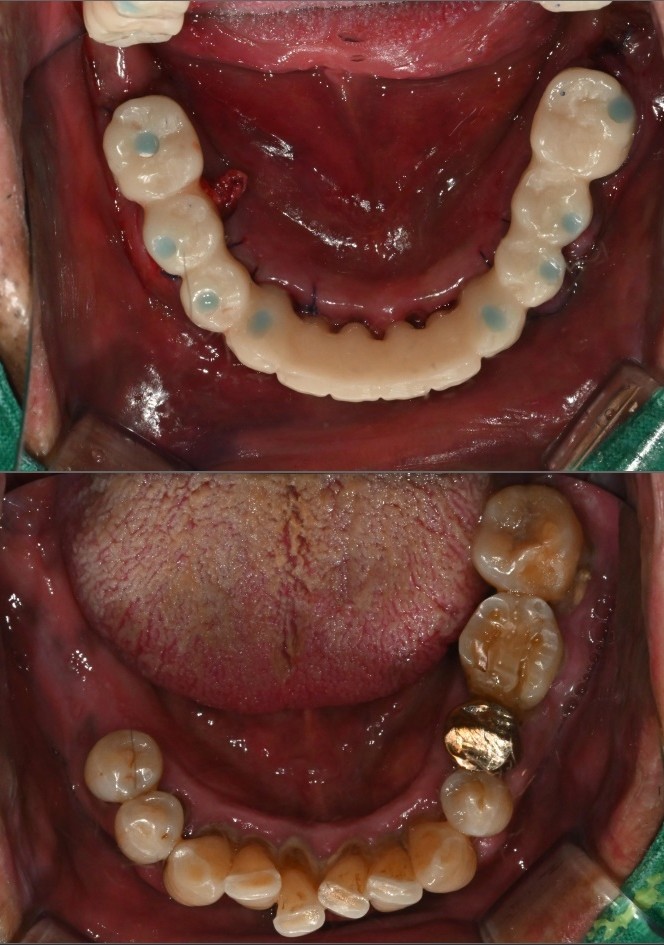

발치 12개임플란트 8개 식립

뼈 상태와 고정력이 안정적으로 나와

다음날 임시치아

바로 장착하기로 결정했습니다.

여기서 중요 포인트는,

잇몸을 누르지 않는 구조의

임시치아 라는 점입니다.

아직 실밥이

선명하게 보이는 시기지만

환자분은 바로

식사와 대화가 가능한 상태가 됩니다.